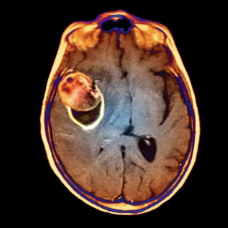

- 뇌종양: 뇌종양이 뇌혈관을 압박하거나 파열시켜 뇌출혈을 유발할 수 있습니다.

뇌출혈은 조기에 발견하고 치료를 시작할수록 예후가 좋습니다. 따라서 뇌출혈 전조증상을 미리 알아두고, 증상이 나타나면 즉시 병원을 방문하여 정확한 진단을 받는 것이 중요합니다.